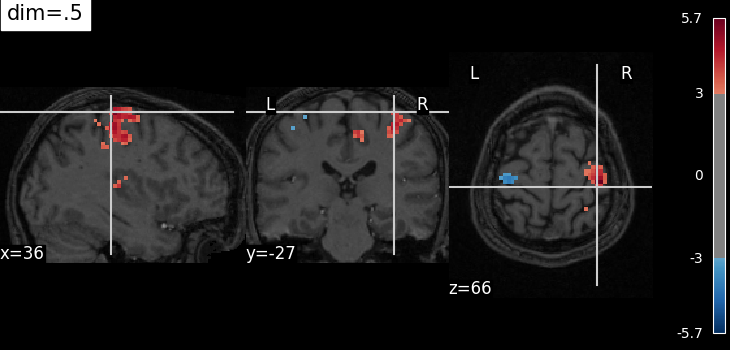

The dim argument controls the contrast of the background.

dim modifies the contrast of this image: dim=0 leaves the image unchanged, negative values of dim enhance it, and positive values decrease it (dim the background).

Plotting with decrease of contrast in background image with dim=.5¶

plot_stat_map(

localizer_tmap_filename,

bg_img=localizer_anat_filename,

cut_coords=cut_coords,

threshold=3,

title="dim=.5",

dim=0.5,

)

<nilearn.plotting.displays._slicers.OrthoSlicer object at 0x7f1ee8606cb0>